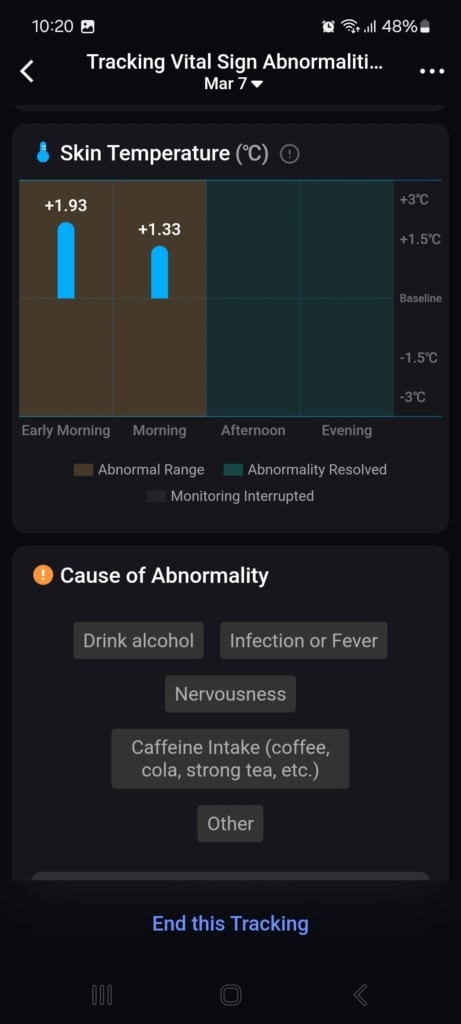

Stan funkcji życiowych (Znaki życia)

W tej części aplikacji dowiesz się o całodziennych wahaniach tętna i jego zmienności, nasyceniu krwi tlenem, częstotliwości oddechów podczas snu i temperaturze snu. Aplikacja porównuje wszystkie te dane z twoją własną referencją z ostatnich 7 do 30 dni oraz z referencyjnymi wartościami medycznymi. Gdy tylko w ciągu dnia lub nocy osiągniesz wartości, które nie mieszczą się w referencyjnych granicach, aplikacja cię o tym poinformuje.

Najczęściej spotykałem się z wyraźnym spadkiem zmienności tętna i wzrostem samego tętna. Te wahania pojawiały się czasem podczas snu, aktywności sportowej lub w przypadkowych sytuacjach, o których nie miałem pojęcia. Mimo że doceniam ten kompleksowy wgląd w moje funkcje życiowe, brakowało mi podczas testowania kontekstu. Funkcja oferuje jedynie wartości i spostrzeżenia, że coś jest nie tak. Nie znalazłem w aplikacji żadnych wskazówek dotyczących możliwych przyczyn ani rekomendacji działań, które mogłyby pomóc przywrócić stan do normy.

Mimo że nietypowe wartości nie mają jasnego kontekstu, aplikacja zwraca na nie uwagę i pyta, co mogło być ich przyczyną (spożycie alkoholu, infekcja, kofeina i inne). W moim przypadku działało to idealnie. Popełniłem błąd dietetyczny, przez który dostałem gorączki i problemów trawiennych. Mój ogólny stan znacznie się pogorszył, co objawiło się wyraźnym spadkiem jakości snu, obniżoną zmiennością tętna i podwyższoną temperaturą ciała. Wszystkie te zmiany zostały przez pierścień i aplikację trafnie rozpoznane i ocenione. Po kilku dniach mój stan się poprawił – również to zostało odnotowane i odpowiednio skomentowane.